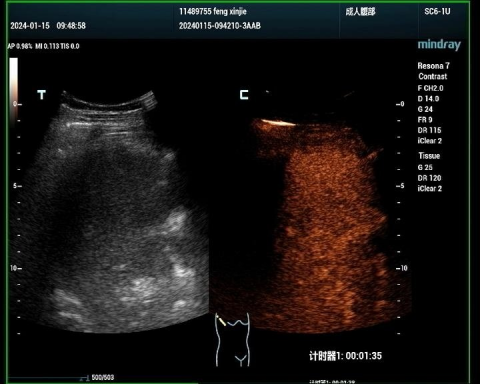

肝血管瘤